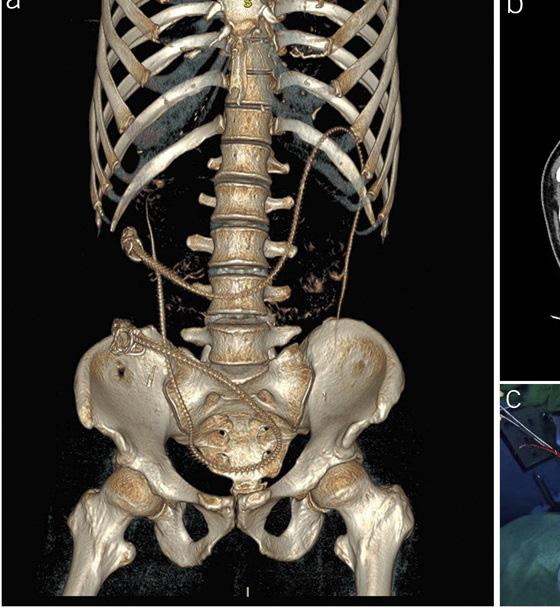

PATIENT HANDOUT: FOCAL LIVER LESIONS

Information for patients to understand growths found on the liver during imaging